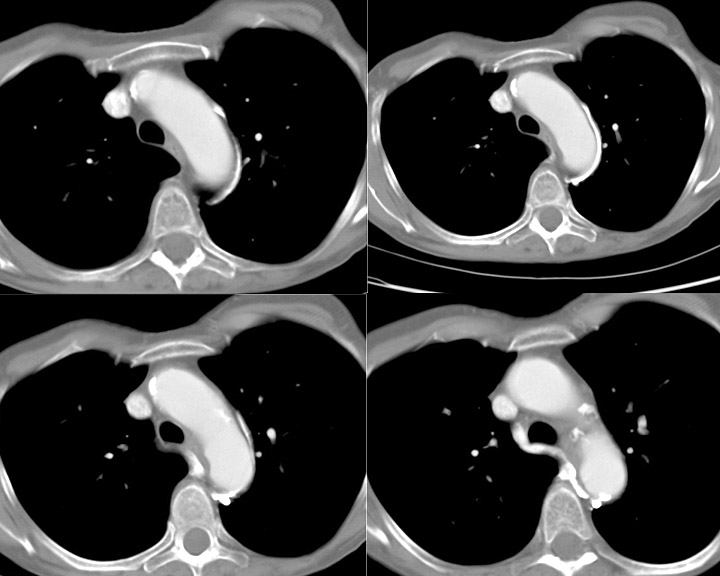

Gallery Normal and Variants Ao nipple CT

Ao nipple CT